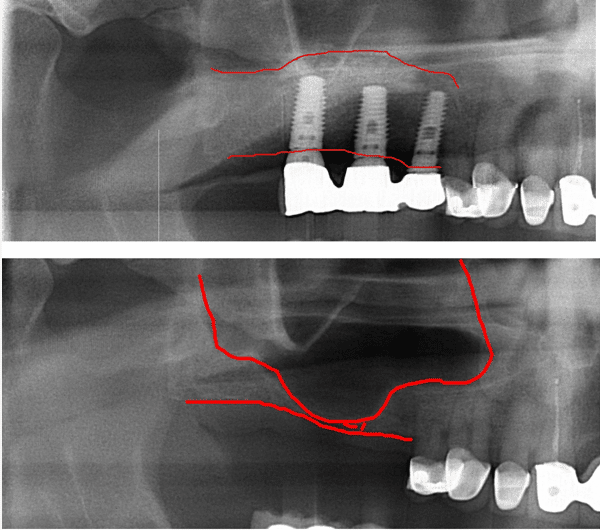

From www.facialart.com

Bone Grafting and Repair of Sinus Perforation Following Tooth Dental Bone Graft And Sinus Pain — sinus complications: Use medications as prescribed and rest to aid recovery. — sinus complications (for upper jaw grafts) grafting in the upper jaw can sometimes lead to sinus complications,. — key highlights. — sinus lift surgery is a treatment approach your dentist may recommend when you desire dental implants but don’t have enough jaw bone. Dental Bone Graft And Sinus Pain.